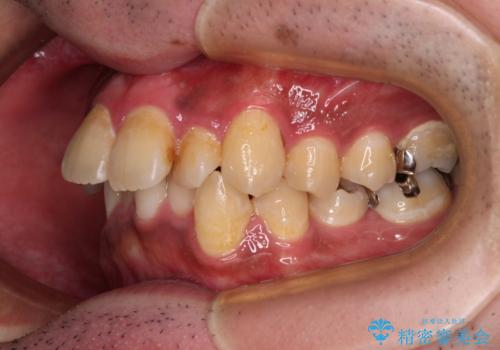

- 主張してる上の前歯を気にして来院された患者様です。

上の前歯が出ているものの、口元が出っ歯というわけではなかったため、非抜歯矯正にて治療を行うこととしました。

下顎に対して上顎歯列が全体的に前方に位置しており、特に右側の奥歯の咬み合わせの前後のズレが大きいため、補助装置を用いて咬み合わせを改善することとしました。